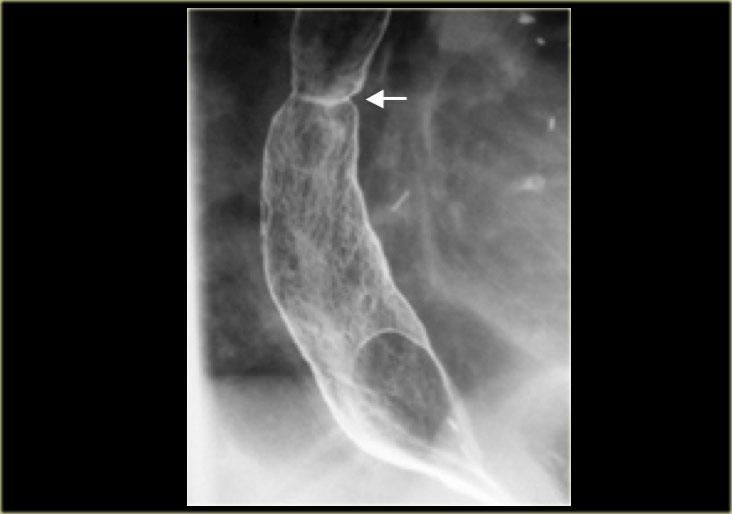

Hình bên trái là một bệnh nhân viêm thực quản tăng bạch cầu ái toan.

Có hình ảnh hẹp lan tỏa đoạn xa và bờ gợn sóng (mũi tên) do các vết lõm dạng vòng nhẫn, đặc trưng của viêm thực quản tăng bạch cầu ái toan.